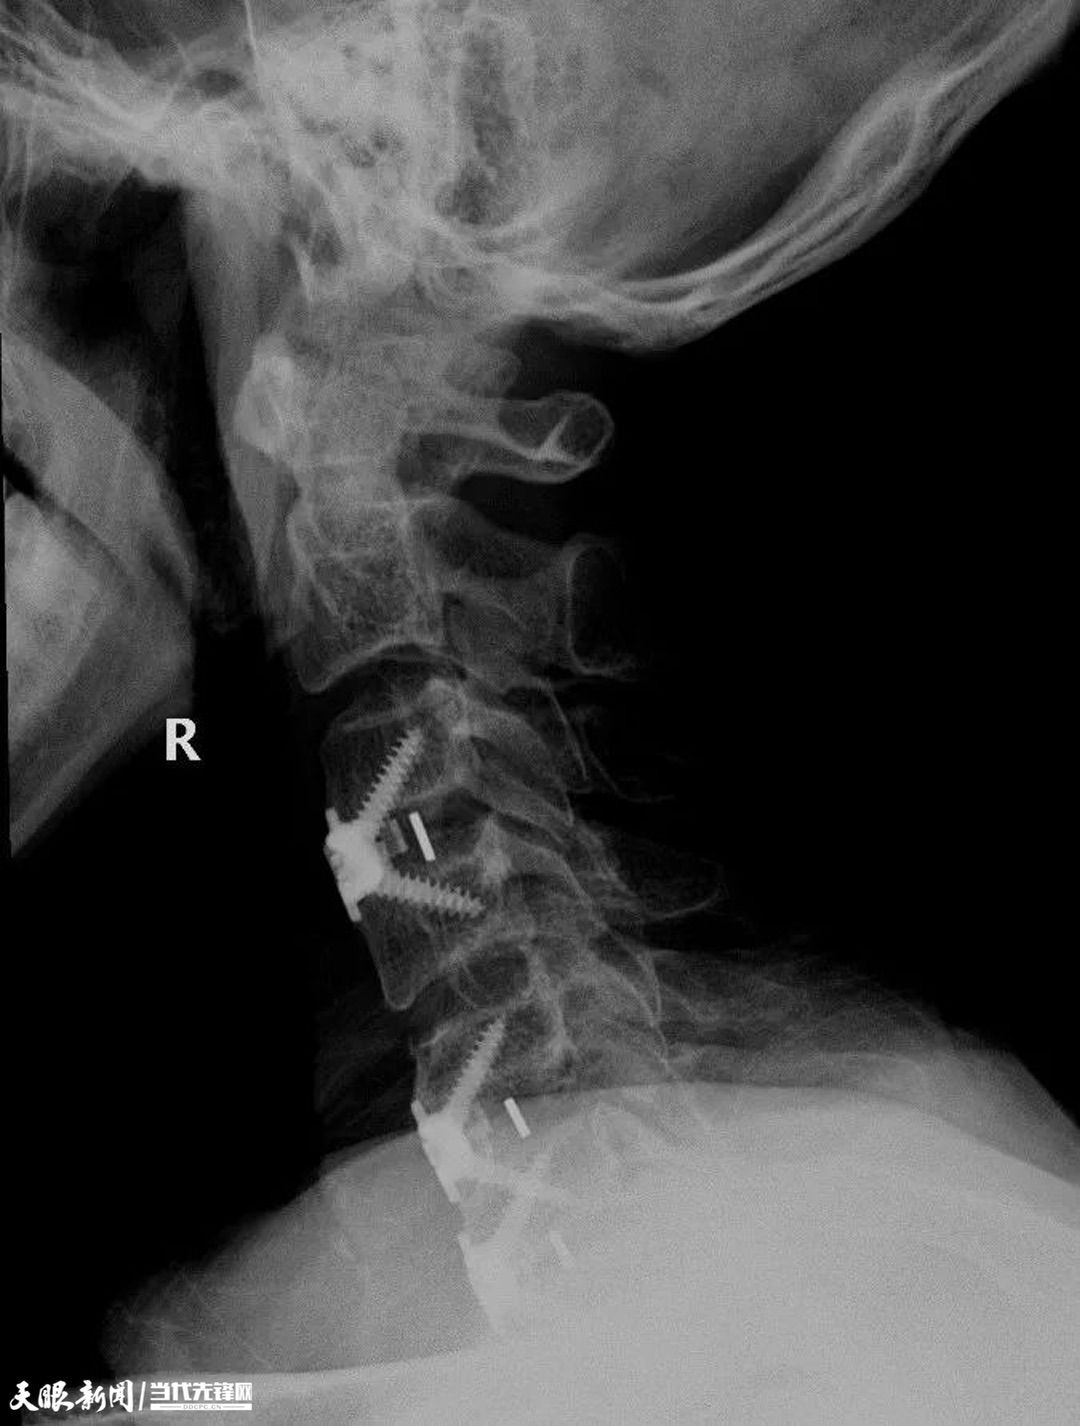

为了保证手术成功,大年三十当天,孔维军亲自为王某主刀,在骨伤科医生团队及多部门通力协作下进行手术。为了这台手术很多人错过了年夜饭,即便大年三十不能够跟家人欢聚一堂,他们也无怨无悔,默默坚守。

术后X片